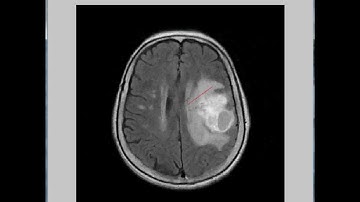

Brain Tumor Detection Quantification MRI DCIOM IMAGES